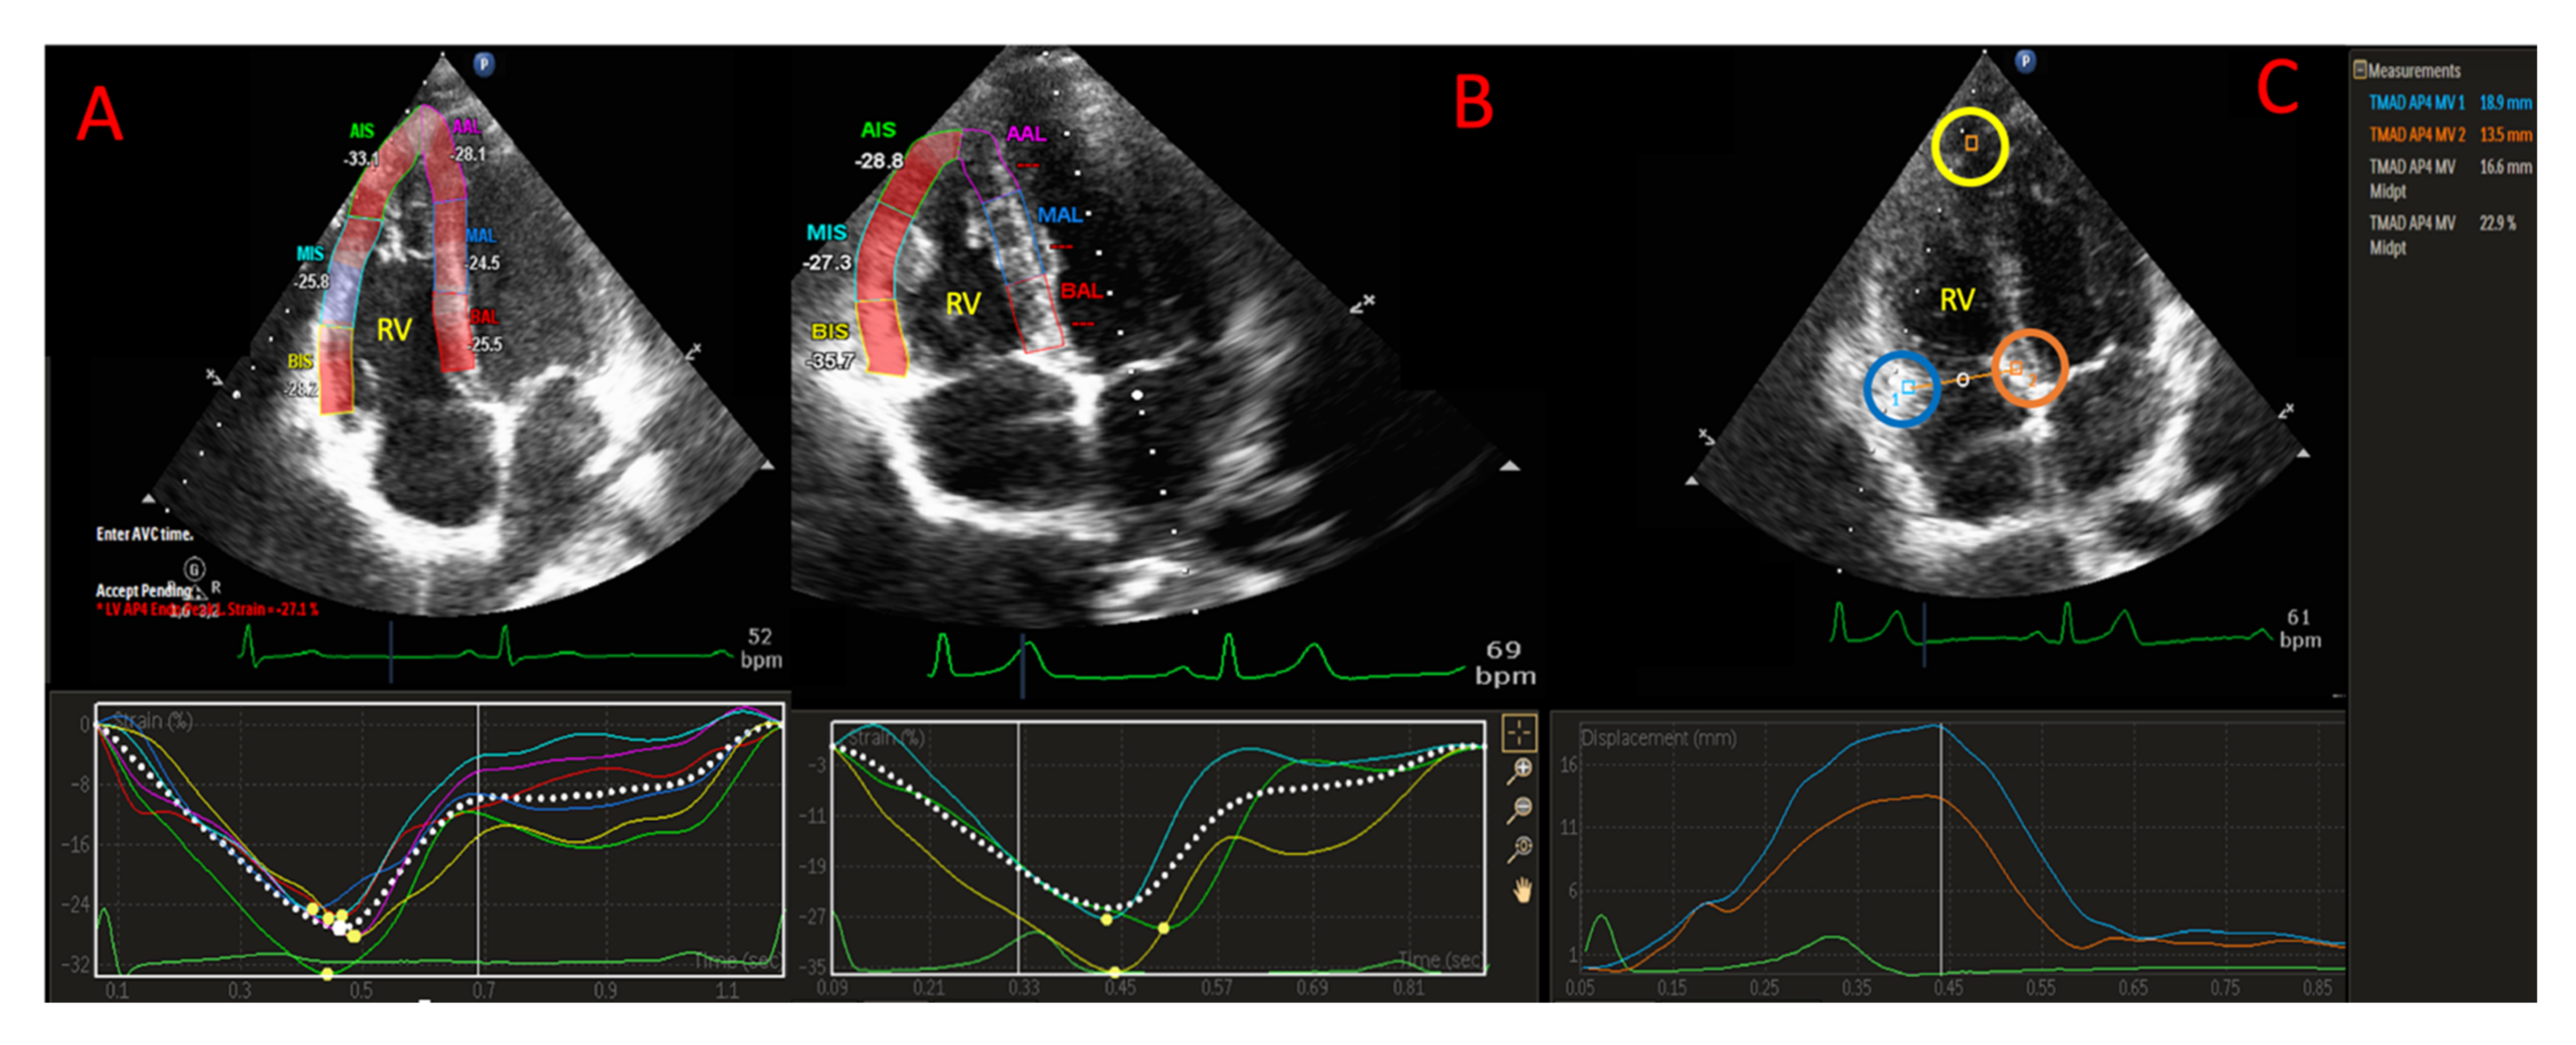

2.5. D-STE Analysis

2.6. RV Strain Analysis

2.7. TAD Analysis